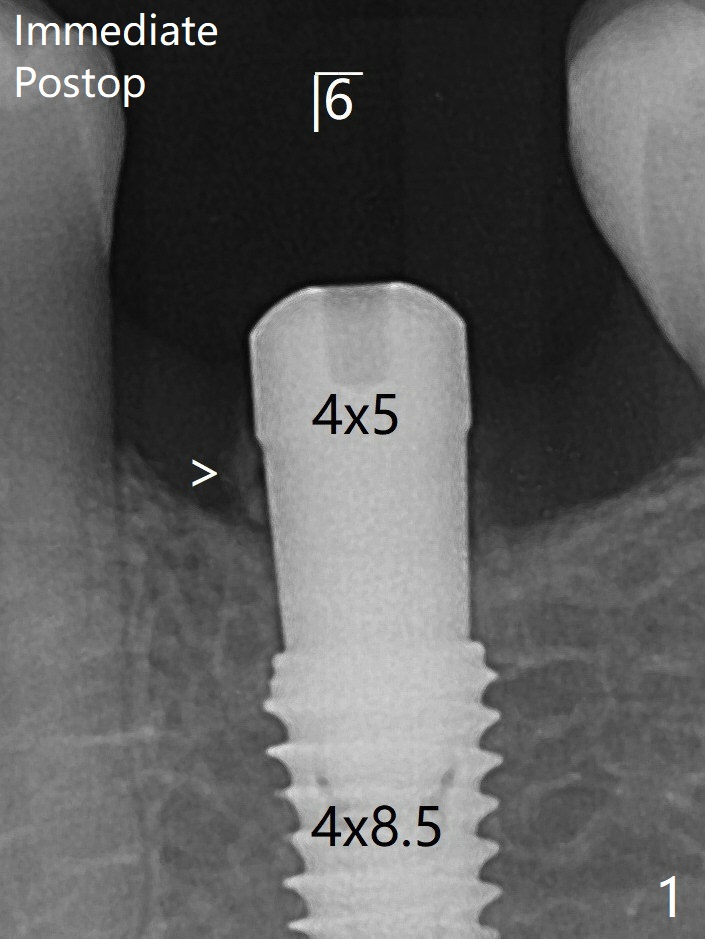

术后7个月左下4毫米修复基台无法就位(图四:箭头),手拧紧螺丝发出响声。